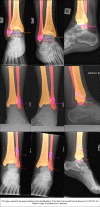

Purpose: Convolutional neural networks (CNNs) are increasingly being developed for automated fracture detection in orthopaedic trauma surgery. Studies to date, however, are limited to providing classification based on the entire image-and only produce heatmaps for approximate fracture localization instead of delineating exact fracture morphology. Therefore, we aimed to answer (1) what is the performance of a CNN that detects, classifies, localizes, and segments an ankle fracture, and (2) would this be externally valid?

Methods: The training set included 326 isolated fibula fractures and 423 non-fracture radiographs. The Detectron2 implementation of the Mask R-CNN was trained with labelled and annotated radiographs. The internal validation (or 'test set') and external validation sets consisted of 300 and 334 radiographs, respectively. Consensus agreement between three experienced fellowship-trained trauma surgeons was defined as the ground truth label. Diagnostic accuracy and area under the receiver operator characteristic curve (AUC) were used to assess classification performance. The Intersection over Union (IoU) was used to quantify accuracy of the segmentation predictions by the CNN, where a value of 0.5 is generally considered an adequate segmentation.

Results: The final CNN was able to classify fibula fractures according to four classes (Danis-Weber A, B, C and No Fracture) with AUC values ranging from 0.93 to 0.99. Diagnostic accuracy was 89% on the test set with average sensitivity of 89% and specificity of 96%. External validity was 89-90% accurate on a set of radiographs from a different hospital. Accuracies/AUCs observed were 100/0.99 for the 'No Fracture' class, 92/0.99 for 'Weber B', 88/0.93 for 'Weber C', and 76/0.97 for 'Weber A'. For the fracture bounding box prediction by the CNN, a mean IoU of 0.65 (SD ± 0.16) was observed. The fracture segmentation predictions by the CNN resulted in a mean IoU of 0.47 (SD ± 0.17).

Conclusions: This study presents a look into the 'black box' of CNNs and represents the first automated delineation (segmentation) of fracture lines on (ankle) radiographs. The AUC values presented in this paper indicate good discriminatory capability of the CNN and substantiate further study of CNNs in detecting and classifying ankle fractures.